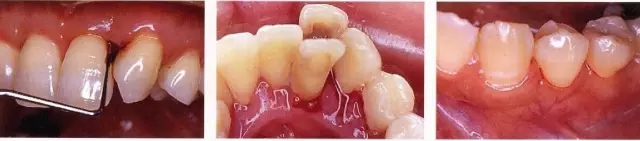

一定要記錄好!探診時(shí)出血

有出血量大的時(shí)候,也有出血量非常少的時(shí)候,無(wú)論哪一種都是炎癥出現(xiàn)的標(biāo)志,要確認(rèn)原因后進(jìn)行對(duì)應(yīng)。